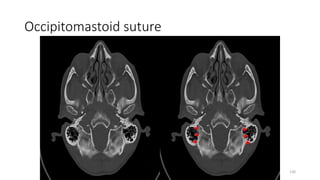

OCCIPITOMASTOID SUTURE

OCCIPITO MASTOID SUTURE